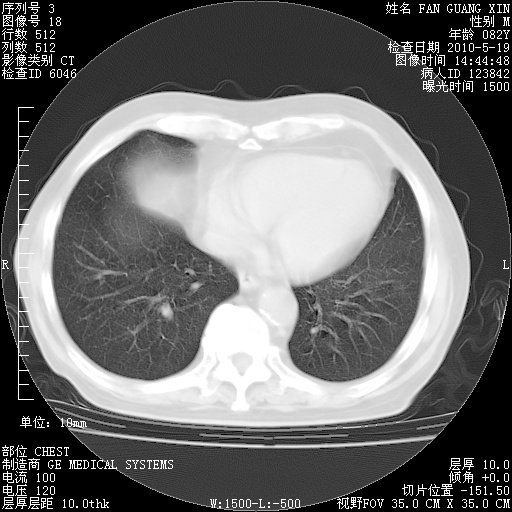

可改为口服强的松40-50mg/d治疗,若病情仍稳定,胸部阴影不再吸收可逐渐减量